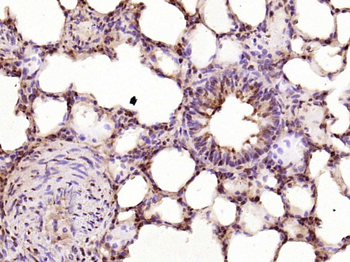

100 μl, 50 μl, 200 μlPhospho-CDKN1A/p21 (Ser130) Rabbit Polyclonal Antibody [orb6571]

FC, IF, IHC-Fr, IHC-P

Mouse, Rat

Human, Mouse, Rat

Rabbit

Polyclonal

Unconjugated

200 μl, 50 μl, 100 μlCDKN1A/p21 Rabbit Polyclonal Antibody [orb11203]